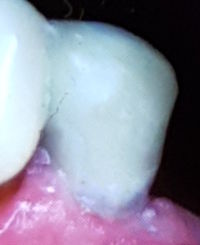

Keilförmige Defekte sind die häufigsten Zeichen von Bruxismus und wie ein kleiner Spiegel der Seele.

Mit kleinen Retentionsgrübchen kann man das Komposit besser retinieren. Der Bruxismus bewirkt in vielen Fällen nach 10-20 Jahren einen zweiten keilförmigen Zahnhalsdefekt unter der Zahnhalsfülung.

79-jährige Patientin (10.07.2025 / 6563)

Das kräftige Beissen hat trotz einer Knirscherschiene diesen Prämolar beim Zahnhals querfrakturiert obwohl er vital und kariesfrei ist.

Porzellan- und Goldkronen sind nicht elastisch wie die Zähne sondern starr, so dass sich die Querkräfte alle am Kronenrand beim Zahnhals auswirken. Dieser Zahnhals hat den Querkräften gewiss 30 Jahre lang stand gehalten.